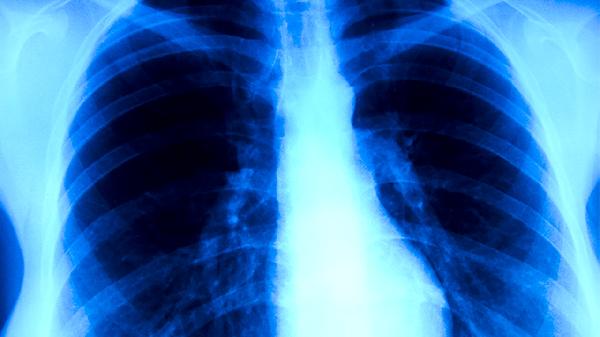

肺癌早期胸痛通常表现为隐痛或钝痛,可能伴随咳嗽、胸闷等症状。胸痛特点主要有定位模糊、间歇性发作、与呼吸相关、程度较轻、无放射痛等。